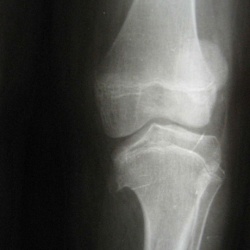

Наблюдение из серии "Травма. Что напишем травматологу?" или "зачем нужны отсроченные снимки?" Пациент один.